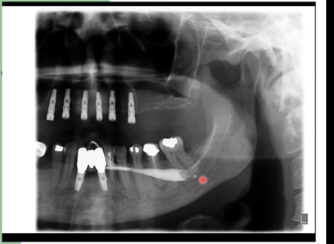

Describe what this sialography procedure contrast radiograph is showing

• Right submandibular gland

• Slight subtle obstructions where red pointer is likely to be mucous plugs

• Stricture of duct towards end

• Duct dilatation towards genome

• Filling defect shows in duct